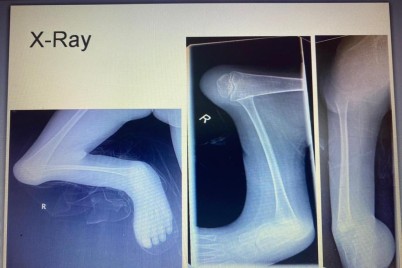

جدة - ريفان هوساوي نجح الفريق الطبي في قسم جراحة العظام بمستشفى الملك فهد العام بجدة بقيادة الدكتور عبدالهادي العمودي...